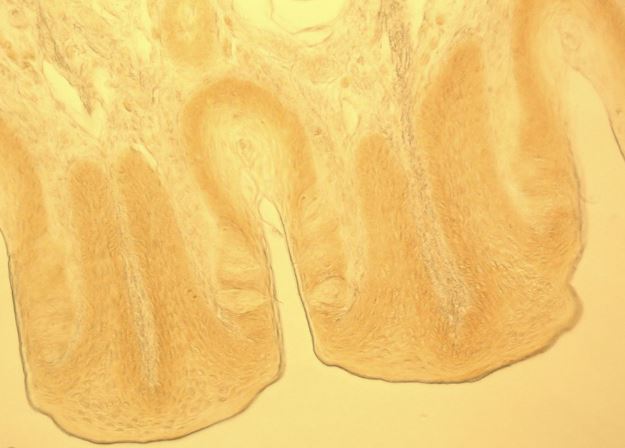

兔子味蕾斷面,相差顯微鏡

兔子味蕾斷面,微分干涉對(duì)比顯微鏡

兔子味蕾斷面,明場(chǎng)顯微鏡